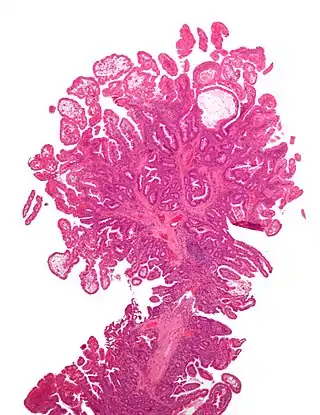

El síndrome de Peutz-Jeghers es una enfermedad autosómica dominante, se caracteriza por la producción y la presencia de pigmentaciones epidérmicas, además de la presencia de hamartomas gastrointestinales; este hecho fue confirmado en 1987 por Giardello, el cual reportó 31 casos de síndrome de Peutz-Jeghers, con daño gastrointestinal asociado a hamartomas.[1]

Generalmente la presencia de estos síntomas como los hamartomas no se considera perjudicial o maligna, pero, en el síndrome de Peutz-Jeghers varios autores han reportado casos con excesivo daño gastrointestinal. La presencia de las pigmentaciones suele ocurrir por el desplazamiento epitelial debajo de la capa muscular.[1]

No existe una presentación típica del síndrome de Peutz-Jeghers,[3] sin embargo, en algunos pacientes suele predominar las hiper pigmentaciones muco-cutáneas acompañados de pólipos intestinales que a su vez desencadenan cólicos gastro intestinales de moderada o severa intensidad, los mismos causan rectorragia ya sea esta oscura (melenas) o clara (hematoquecia).[5]